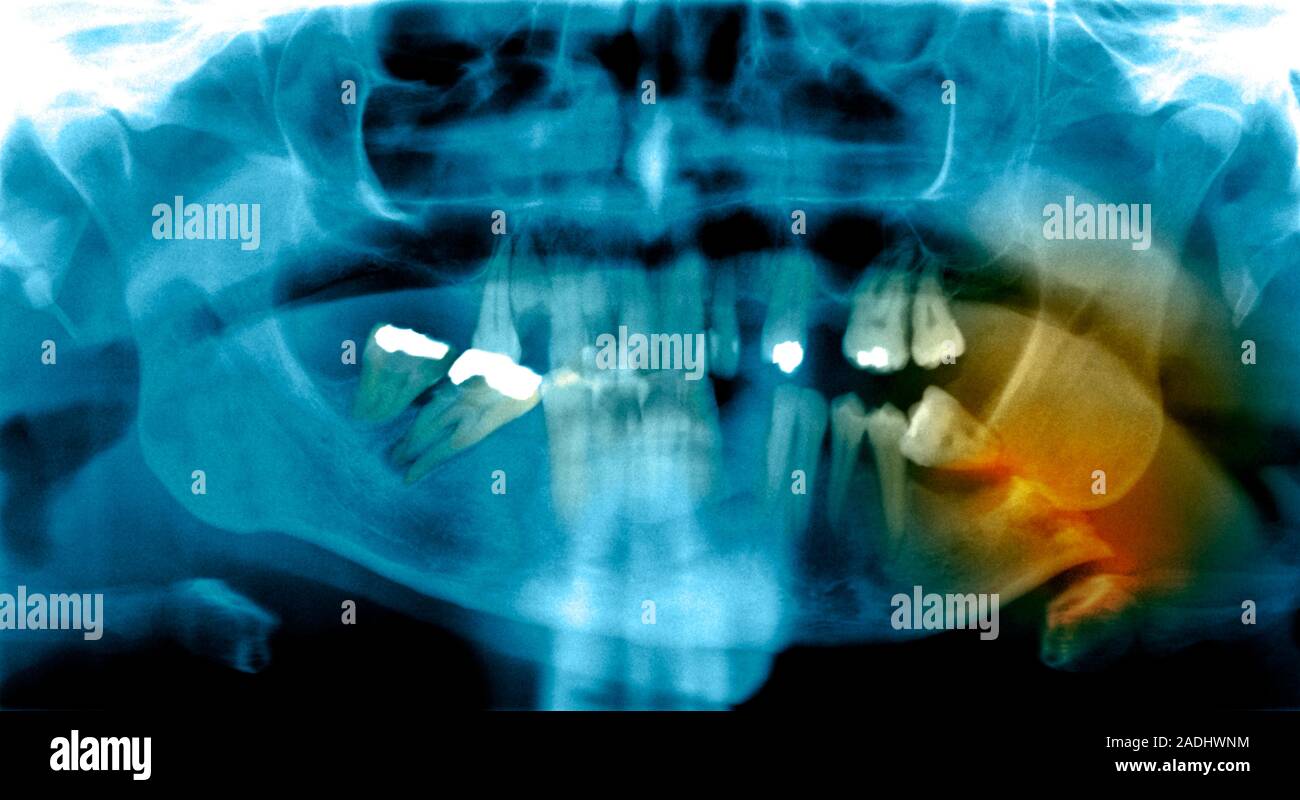

From www.alamy.com

Fractured jawbone. Coloured Xray of a human jaw showing a fractured What Does A Fractured Jaw Bone Feel Like What does a broken jaw look like? • bleeding from your mouth. The appearance of a broken jaw can vary; A broken jaw (or mandible fracture) is a common facial injury. It might show visible signs of swelling, bruising, or an abnormal jaw. Get the facts on treatment and find out what to eat while you recover. • pain, swelling. What Does A Fractured Jaw Bone Feel Like.